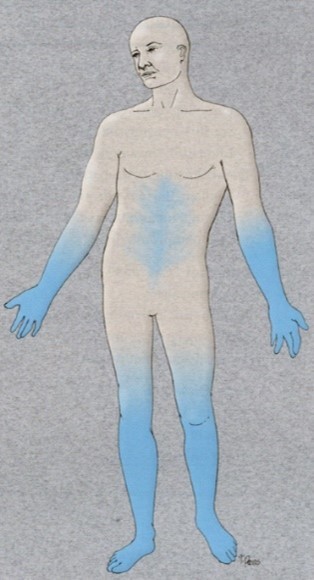

Vad innebär polyneuropati?

Flernervssjuka

- Beskrivande term för symmetrisk funktionsnedsättning av nervtrådar i armar och ben med bortfalls- och/eller retningssymptom som följd

Polyneuropati (flernervssjuka)

- Beskrivande term för symmetrisk funktionsnedsättning av nervtrådar i armar och ben med bortfalls (känsel)- och/eller retningssymptom (ingen smärta) som följd

Vilka symptom kan ses utöver ovan?

- Symptom (nedsatt känsel/smärta mfl) som ovan och två av följande

- Svaga eller bortfallna reflexer

- Nedsatt distal muskelkraft eller atrofi

- Nedsatt distal känsel

- Symptom från känselnerver

- Nedsatt känsel (domnad ”död” känsla)

- Som att gå på kuddar vilket ger dålig balans (yrsel), stickningar (som att gå i nässlor, sockerdrickskänsla), brännande eller isande känsla, smärta, åtkramande besvär, ovanlig känslighet för beröring

- Symptom från motoriska nerver

- Nattliga vadkramper, svaghet i händer och fötter (svårt att stå på tå eller häl), atrofi

- Snubblar lätt i ojämn terräning, svårigheter att hålla balansen i mörker (att gå på toa på natten)

- Symptom från autonoma nerver

- Nedsatt svettning, ortosatism, nattlig diarré, svårigheter att urinera, förstoppning och impotens

När kan detta ses?

Polyneuropati